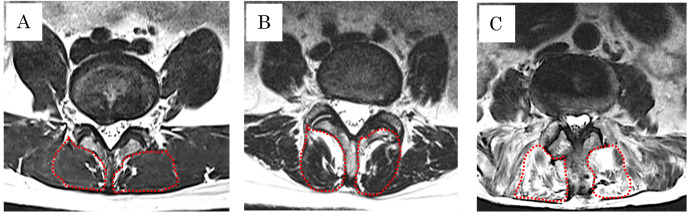

Methods: This study included 177 patients with preoperative LSS, of whom 16 had OVCFs and 161 did not. Lumbar lordosis angle, fat infiltration, and paraspinal muscle atrophy were evaluated in these patients. Information on patient characteristics such as smoking, diabetes, hemodialysis, steroid use, American Society of Anesthesiologists score, and bladder or bowel dysfunction were obtained from medical records. Logistic regression analysis was conducted to identify factors independently associated with OVCF.

Results: Patients in the OVCF group were significantly older (P=0.006) than those without fractures, and a higher proportion of the OVCF group showed muscle atrophy (P=0.034). Significant variables and those with moderate effect sizes were included in the logistic regression analysis. Muscle atrophy (P=0.028) was independently associated with OVCF.